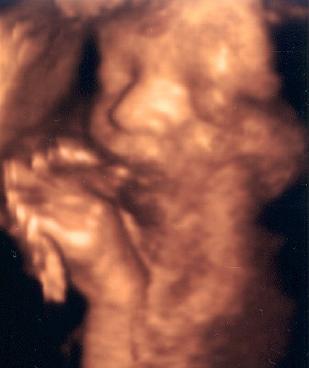

Reni: ügyesen megcsináltad a képet, szépen látszik a kis pofija

bellerreni: Nagyon édes a babó a képen.

Reni, édes a kölök. :) De miért is van ki a t.k.d?

Reni: cuki a kispasid!!!!!

Reni! A kispasid gyönyörűséges! :)

Reni, édi a pici fiacskád :D Ne idegeskedj tovább a mai napon, a terhesség alatt uis kiszámíthatatlanok vagyunk érzelmileg.

Reni: nagyon jó fotó lett a babáról! :)

Szép kis husibaba :D